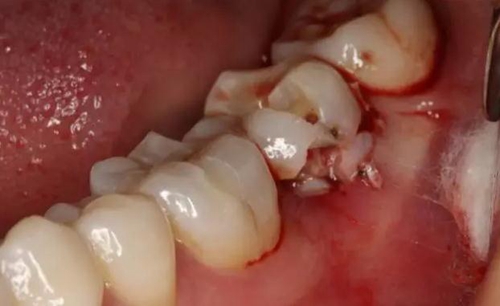

圖2.  37牙冠基本完好,松動(dòng)Ⅰ度。合面有一開髓孔被棉球覆蓋,頰側(cè)牙齦輕度紅腫。

2.jpg

圖3.   取出棉球口內(nèi)發(fā)現(xiàn)37合面有開髓孔,探針出血,頰側(cè)牙齦紅腫。

3.jpg